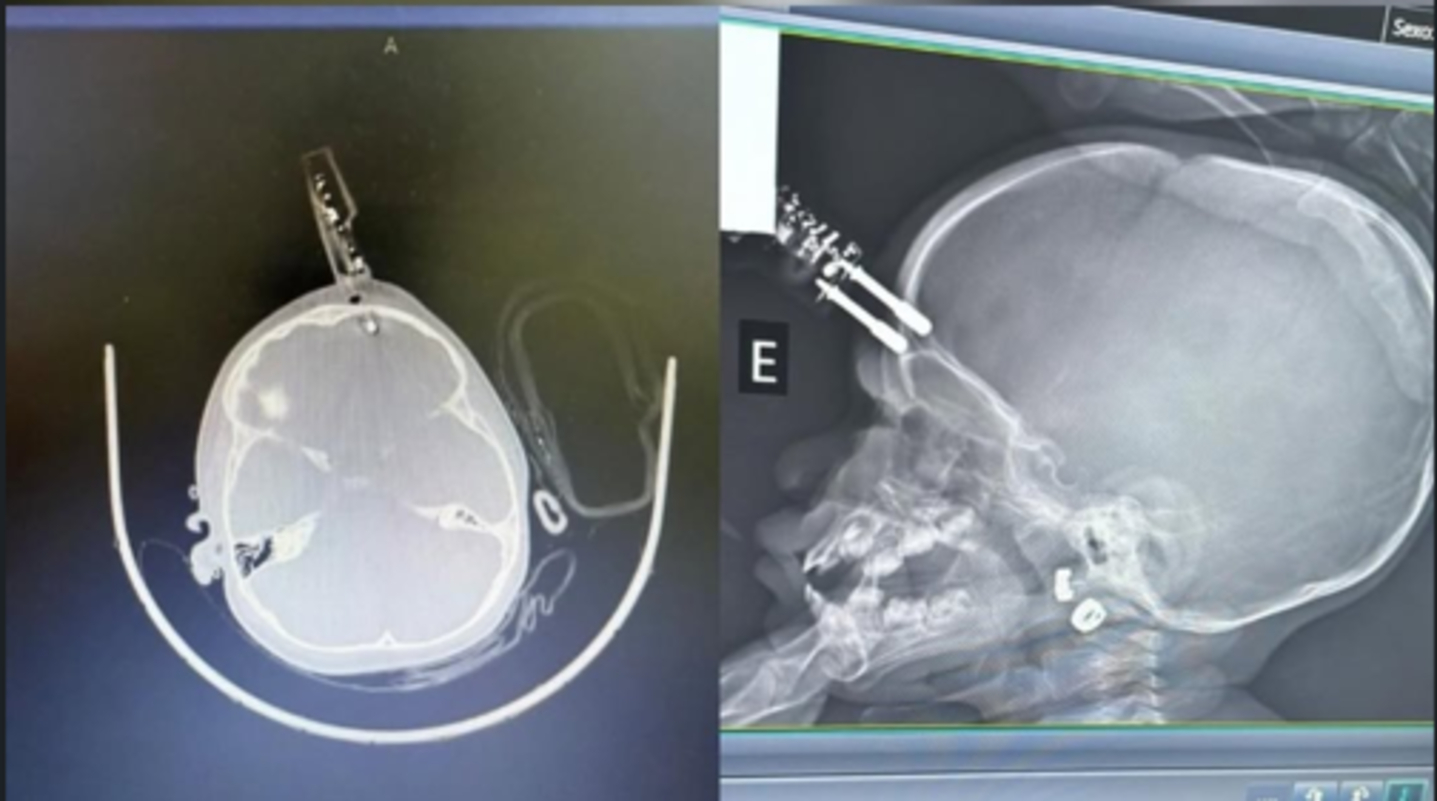

Bebê de 1 ano cai da cama e fica com carregador cravado na testa em MG